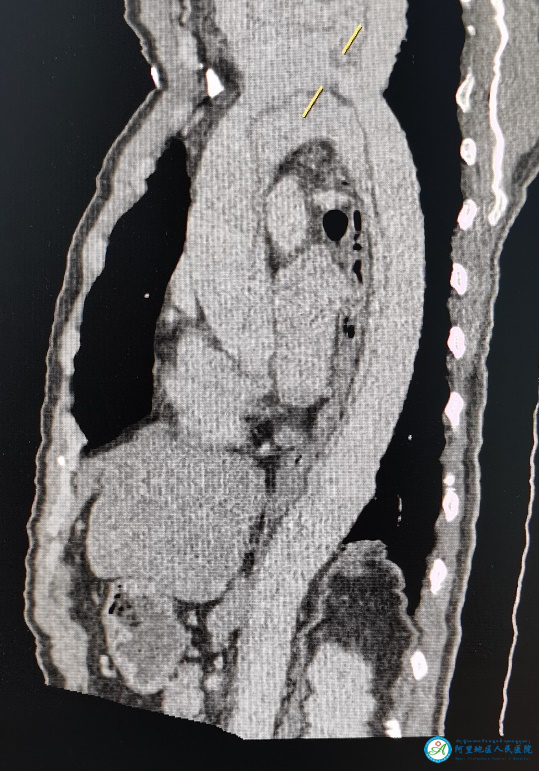

10月23日,阿里地區(qū)人民醫(yī)院急診科收治了一名急性胸痛患者,經(jīng)胸痛中心羅永百教授會診,高度懷疑主動脈夾層。這是一種極度兇險的疾病,確診需要進行主動脈的增強掃描。放射科援藏醫(yī)生劉正華在和羅教授溝通后,克服高壓注射器不能配套使用的難題,采用手動推注造影劑,完成了放射科第一例主動脈夾層的CT增強掃描,實現(xiàn)了阿里高原上CT增強掃描“零”的突破。